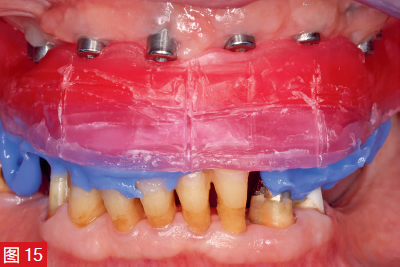

上頜骨4顆以下的成活率為69.7%,而4顆種植體的成活率顯著提高至89.1%。因此,可以推薦在下頜種植 1、2 或 4 顆種植體,從而提高成功率。對于上頜活動義齒,應計劃至少 4 顆種植體。如果將目前的數據情況與 25 年前的圖 15 中的治療方案進行比較,下頜骨和上頜骨將顯示出明顯的差異。有一種觀點認為,在下頜中,可以借助球帽附件將種植體放置在中間以保留覆蓋義齒(圖 8 和 9)。但是,對于上頜,有兩個植入物保留)當前研究不再涵蓋這種情況。上頜骨至少需要 4 個種植體,

全數字化工作流程尚未經過充分的科學研究,因此不推薦用于臨床。此外,使用數字印模系統獲得的結果難以轉移到另一個印模系統,使得該領域難以獲得合理的臨床數據。1993 年對金屬底架制造的描述至今仍然有效,其內容如下:“可鑄造的金合金塊 [...] 用作底架制造的基礎 [...]。完成的底架蠟-up 可以修整澆注,也可以分幾部分澆注。如果分幾部分澆注,則必須在口內固定并在實驗室焊接在一起。[…]因此,整個基架必須達到應力-自由搭配。” 現在,由于CAD/CAM技術與角螺釘固定相結合,大大簡化了上述過程。借助 CAD/CAM 技術在外部銑削中心上加工鈷鉻基架。在患者身上試戴的預排牙可作為此基架設計的依據(圖15至16)。如有必要,制造時應考慮角螺釘固定基礎框架(圖 17)@)。>.基于此制造工藝,即使基礎框架的跨度和范圍很大(圖 18 和 19),并且也避免了對普通焊接或激光焊接的需要。

圖 15:確定牙槽與蠟庫的關系,蠟庫由旋入式牙齦成型器上的樹脂基底支撐。從水平面、垂直面和矢狀面調整蠟堤,并標出中線、嘴線、唇線,以便輕松微笑和大笑。然后使用

記錄由樹脂(藍色;DMG,德國)固定確定的頜關系。